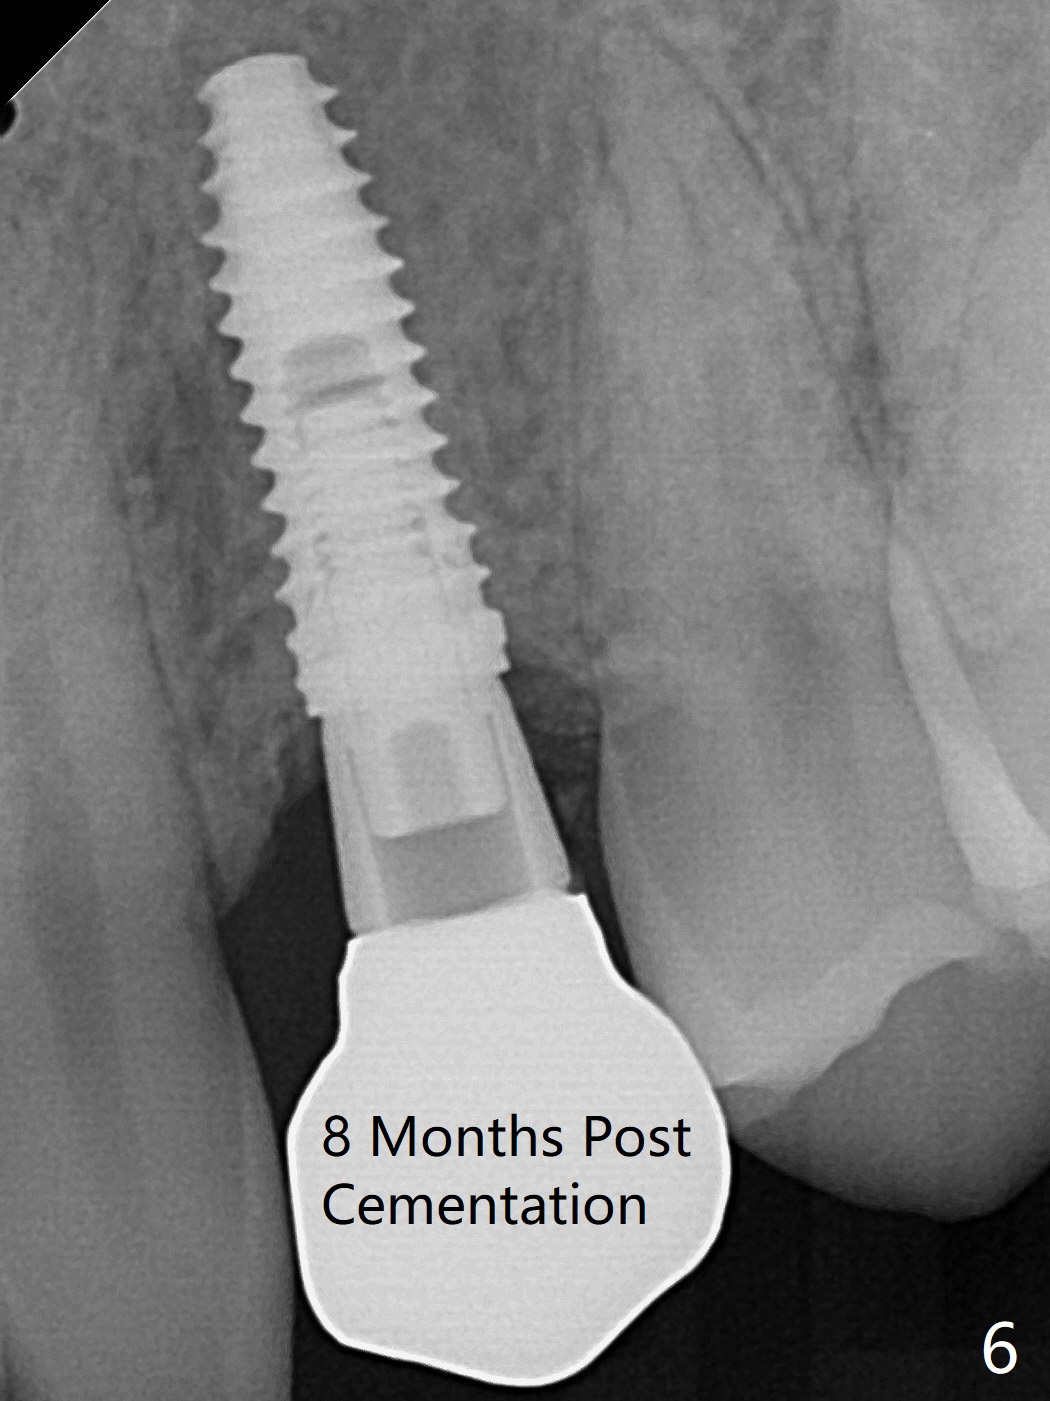

When the guide with 10.5 mm offset is seated at #11 after extraction, it looks buccal. Pointed drill creates an entry point in the mesial portion of the socket. PA, taken following 2.2x11.5 mm drill, shows acceptable mesiodistal trajectory (Fig.1). When a 3.5x11.5 mm implant is placed, it is difficult to withdraw the driver from the metal tube (Fig.1 *). There is no buccal gap with plenty of the lingual gap. A 4x3 mm x15 degree A-type angled abutment is placed (Fig.2). It appears that the dense palatal plate deviates the osteotomy and implant placement (as compared to the design, Fig.3). In fact osteotomy should have been prepared until 4 mm in diameter before increase in depth with 2.2 and 3 mm drills to eliminate buccal deviation. The ideal drill sequence would be point drill, 2.2x8.5 mm drill, 3x8.5, 3.5x8.5, 2.2x10, 2.2x11.5, PA to confirm trajectory, 3x10, 3x11.5 and 3x13. Torque associated with implant placement is pure, not derived from friction between the driver and the metal tube. There is mesial crestal bone loss 4 months postop (Fig.4, as compared to immediate postop in Fig.2 (*)). Crestal bone loss does not get worse between 4 and 6.5 months postop (Fig.4,5). The bone density increases 8 months post cementation (Fig.6).